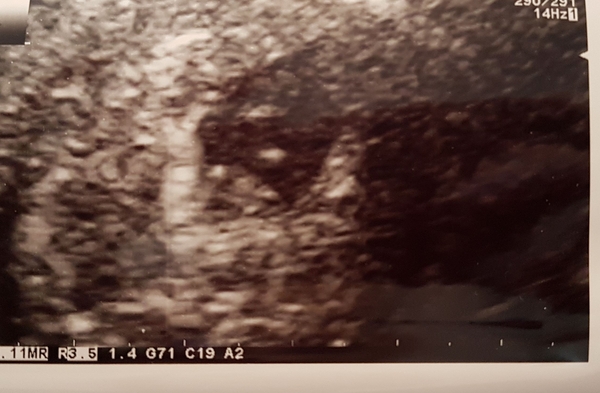

And here it is one early scan....spot the baby!

September 2018 #2: testing and symptom-analysing

Love that scan photo Namechangedtoscream. I’m booking in for a private scan now at about 9-10 weeks so I can get a photo as our EPU doesn’t give them. Had a vaginal ultrasound today so saw our little blob clearly but want to wait a little more for an abdominal. No idea when I’ll have a dating scan next as EPU are happy to let me wait for an appointment. Should be speaking to a midwife about a booking in appointment tomorrow.